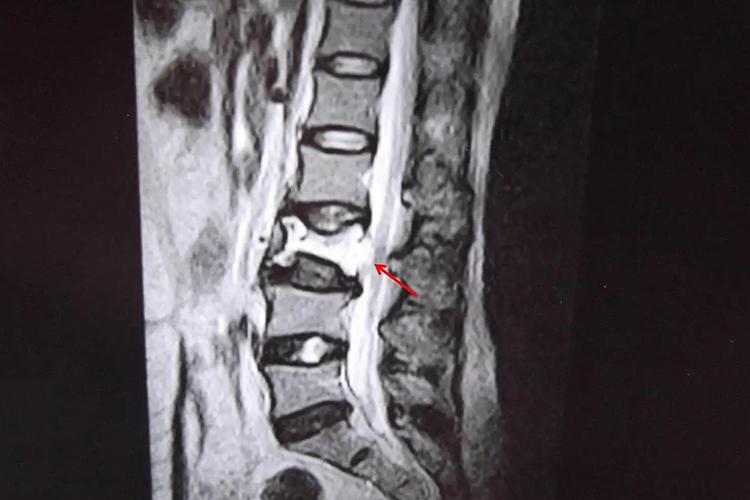

L2椎体血管瘤是一种发生于脊椎的良性肿瘤,其严重性主要取决于血管瘤的大小、生长速度以及是否对周围组织造成压迫,还应及时明确疾病,判断自身是否出现不适症状,并且选择合适的方法进行针对性处理。

- 通常情况下,体积较小的L2椎体血管瘤并不严重,往往不会引起明显的临床症状。这类血管瘤可能是在进行常规的影像学检查时偶然发现的,由于没有对身体造成实际影响,因此不需要特殊的治疗,只需定期复查以监测其变化即可。

- 但是如果自身L2椎体血管瘤逐渐增大时,可能会挤压椎体神经及脊间韧带,导致背部酸胀疼痛、脊椎僵直活动受限等症状。血管瘤的严重性增加,可能需要采取积极的治疗措施。

- 如果血管瘤持续增大并压迫脊髓或神经根,可能导致神经功能障碍,如肢体麻木、无力、大小便功能障碍等,甚至可能出现瘫痪等严重后果,此时病情非常严重,还应及时进行手术治疗,改善症状,以免影响自身健康。